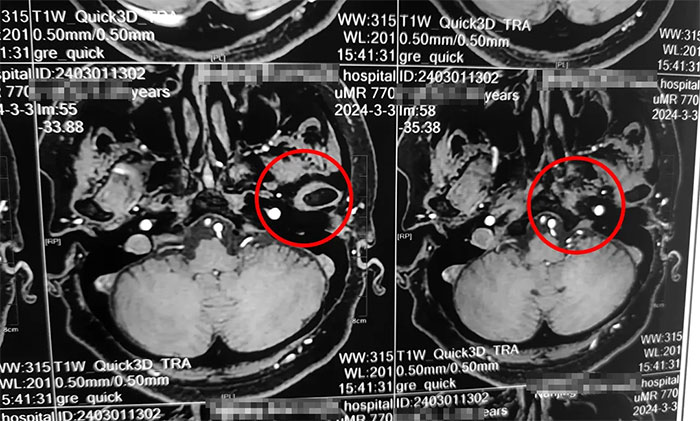

楊忠旭教授詳細了解了劉阿姨的癥狀、病史資料、影像資料等。楊忠旭教授分析指出,傳統(tǒng)的三叉神經(jīng)痛大多發(fā)生于面部,而劉阿姨疼痛的部位為舌頭,和最普遍的三叉神經(jīng)痛位置大相徑庭,但其實支配舌前2/3的感覺的舌神經(jīng),也是自三叉神經(jīng)發(fā)出,所以此處的疼痛完全符合三叉神經(jīng)痛的表現(xiàn)。結(jié)合影像資料,楊忠旭教授指出患者左側(cè)三叉神經(jīng)根部與臨近小血管關(guān)系密切,手術(shù)指征明顯,未見明顯手術(shù)禁忌癥。

▲ 左側(cè)三叉神經(jīng)與臨近小血管關(guān)系密切